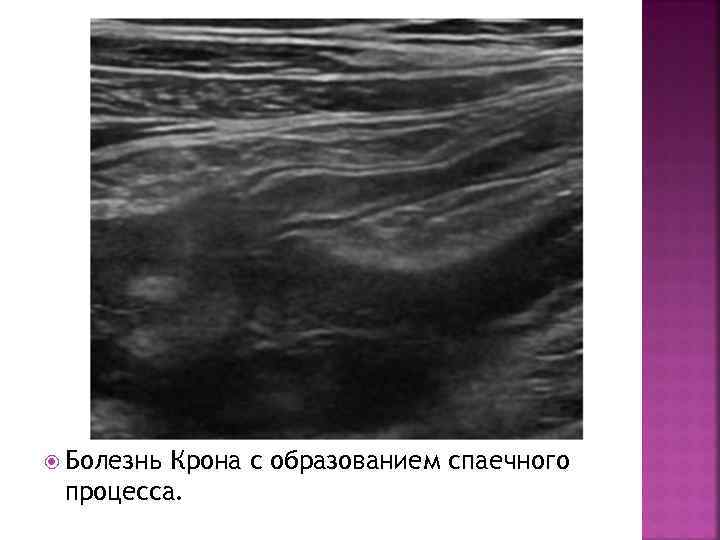

Болезнь Крона с образованием спаечного процесса.